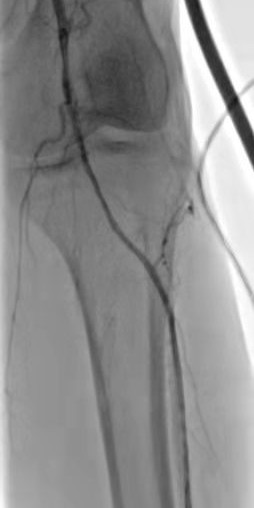

箭头所示:右腘动脉血栓栓塞,血流中断

术后右下肢动脉血流复通

箭头所示:左股、腘动脉血栓栓塞,血流中断

术后:左股腘动脉血流复通